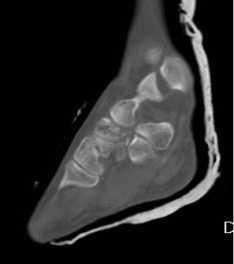

CT can help define the morphology of the MT head, especially when planning osteotomies (Figure 4).

Figure 4: sagittal CT slice through the 2nd MTPJ showing the relative involvement of the dorsum of the head; this illustrates how a dorsal wedge resection osteotomy would rotate articular surface into contact with the base of the proximal phalanx